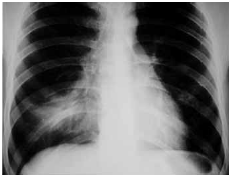

Mulher de 46 anos de idade, previamente hígida, há 3 dias queixava-se de tosse, febre, dispnéia e expectoração amarelada, resolvendo procurar o pronto-socorro. Ela negou etilismo ou tabagismo. Ao exame físico: corada, hidratada e febril (38,1 ºC); PA: 110 x 70 mmHg, FC: 96 bpm, saturação de oxigênio: 94% e frequência respiratória: 20 ipm; ausculta pulmonar: crepitações no terço médio de hemitórax direito. Cardíaco e abdome: normais. Radiografia de tórax: mostrada a seguir.